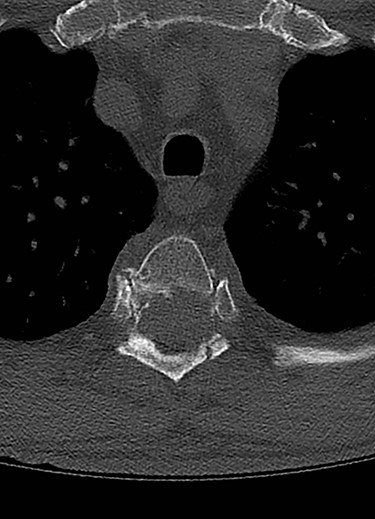

Spinal images are presented in Figs 1–6. Cross-sectional imaging revealed no other neoplastic lesion. He received dexamethasone 10 mg bolus then 4mg four times daily with appropriate proton pump inhibitor coverage. Due to no distinguishable major arterial feeder upon review of the imaging jointly with the neuroradiologist, pre-operative embolization was not attempted. The following morning, he underwent posterolateral right costotransversectomy, ligation of the ipsilateral T4 nerve root, T4 vertebrectomy and insertion of an expandable titanium cage with T1–T7 pedicle screw fixation (Figs 7 and 8). Post-operatively his pain improved to VAS 2/10 and motor power in his left lower limb improved to MRC grade 4/5. The patient was discharged home Day 10 post-admission with physiotherapy.

Sagittal computed tomography (CT) scan demonstrated multiple lytic lesions and pathological fracture of the T4 vertebra with almost complete collapse along with kyphotic deformity.